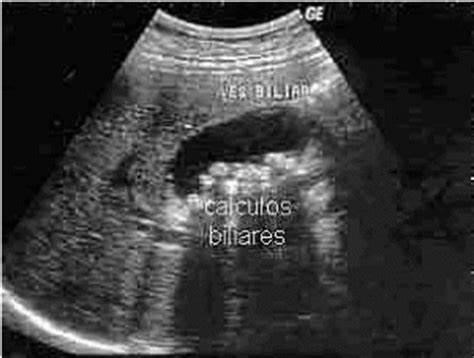

Publicada 23 de setembro de 2019 com 474 × 358 em Vesícula biliar – cálculos e pólipos Curtir Carregando... ‹ Retornar para o post Deixe um comentário Cancelar resposta Δ